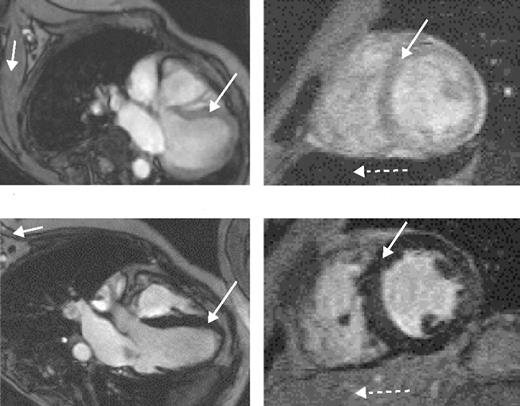

The value of liver iron, whether > 15 mg/g or in the range of 7 to 15 mg/g, as a predictor of cardiac iron has recently been questioned. MRI data using the T2* technique (Figure 5 )9 and spin-echo10 have shown no correlation between cardiac and liver iron, although other MRI techniques, possibly less sensitive and accurate, have shown such a correlation. Possible explanations for these discrepant observations have been discussed.3,9

Cardiac iron

Direct measurement of cardiac iron by endomyocardial biopsy of the right atrium is inappropriate since iron locates mainly to the myocardium of the ventricles. The recent development of a reproducible, sensitive, and accurate indirect measure of cardiac iron using the MRI T2* technique11 has provided substantial important new data. A T2* value less than 20 ms has been found to correlate with the presence of cardiac dysfunction, detected by echocardiography, 24-hour monitoring, or the need for cardiac therapy. It is also valuable for monitoring changes in cardiac iron during intensive chelation therapy.12

Magnetic resonance scans in patients with thalassemia major.Left scans are horizontal long axis, the right ones mid-short axis. (A) Low myocardial iron deposition. The left ventricular volumes are normal, and myocardial signal intensity (long arrow) is similar to that arising from skeletal muscle (short arrow). Left ventricular ejection fraction was 70%. In this case, the liver is very dark (dotted arrow), indicating heavy hepatic iron deposition despite the normal myocardial appearances. (B) Severe myocardial iron overload. The myocardial signal intensity is dark (long arrow) compared with skeletal muscle (short arrow). The ventricle is dilated and thickened. Cine imaging showed greatly reduced systolic function (left ventricular ejection fraction 39%) with a restrictive filling pattern. Liver signal in this case is well preserved (dotted arrow).

Reproduced with permission from